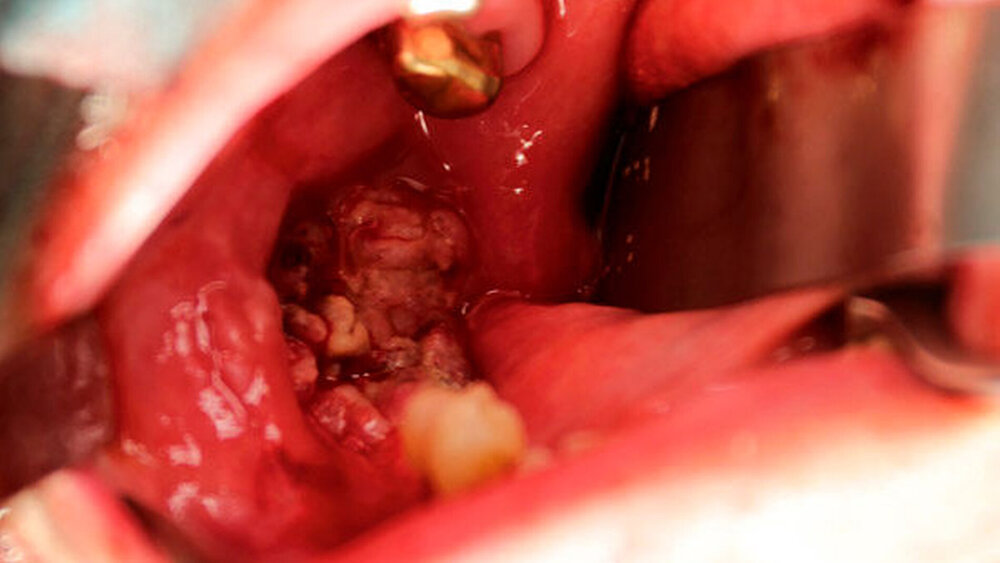

Im November 2019 stellte sich ein 74-jähriger Patient zur Weiterbehandlung eines alio loco histologisch gesicherten Plattenepithelkarzinoms (PEC) regio 048 in unserer ambulanten Sprechstunde vor. Intraoral zeigte sich ein ulzerierender, derbe wachsender, dezent schmerzhafter Tumor mit beginnender ipsilateraler Vincent-Symptomatik (Abbildung 1).